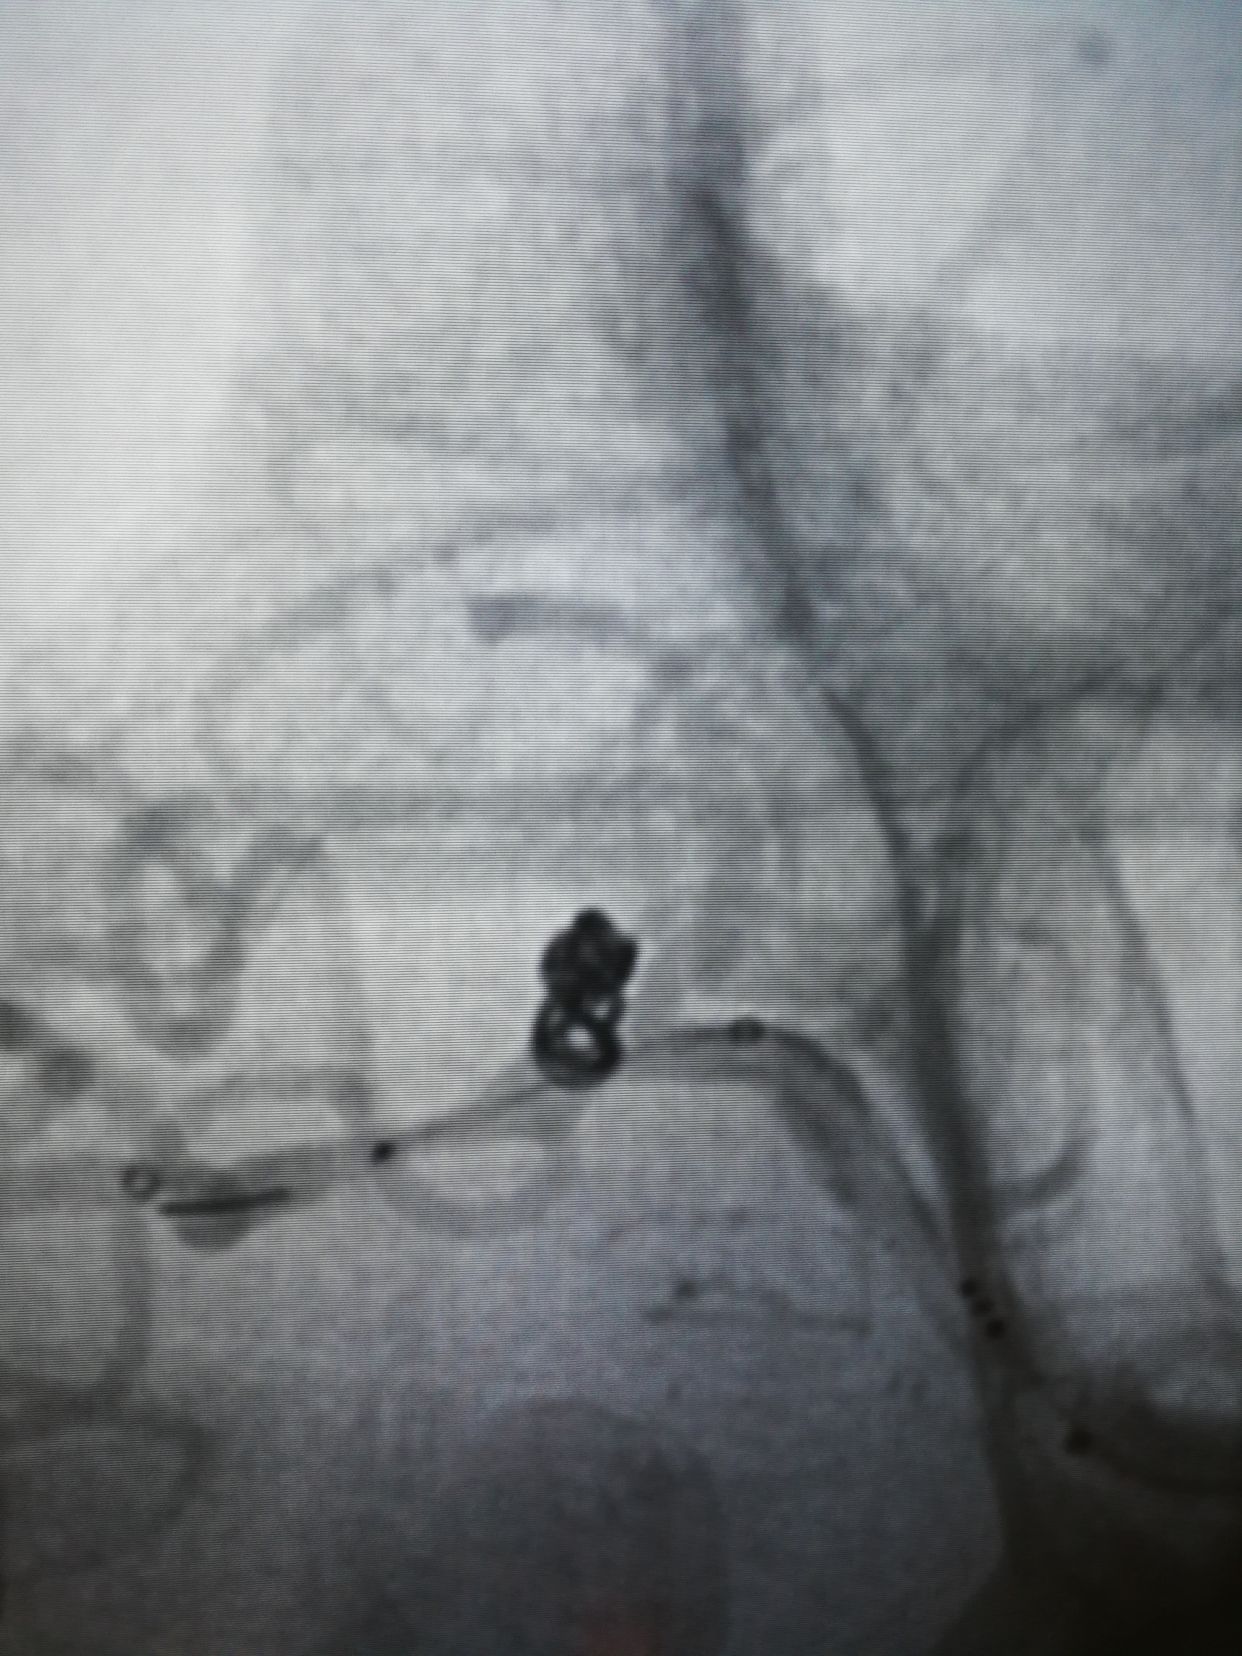

comos 3-6,hypersoft 1.5-3填塞后,成篮还不错,下干几个袢,支架后释放很放心

lvis25-17,支架打开很好,术后动脉瘤完全不显影。1个半小时结束战斗,收工回家。